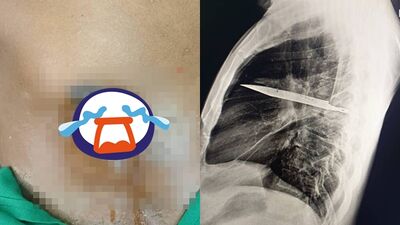

坦尚尼亞發生罕見病例,一名44歲男子右側乳頭附近持續流出惡臭膿液,嚇得趕緊就醫。他接受X光檢查才發現,胸腔內竟藏有一把刀子,估計已經長達8年之久。此病例研究被發表在《外科病例報告期刊》(JSCR)。